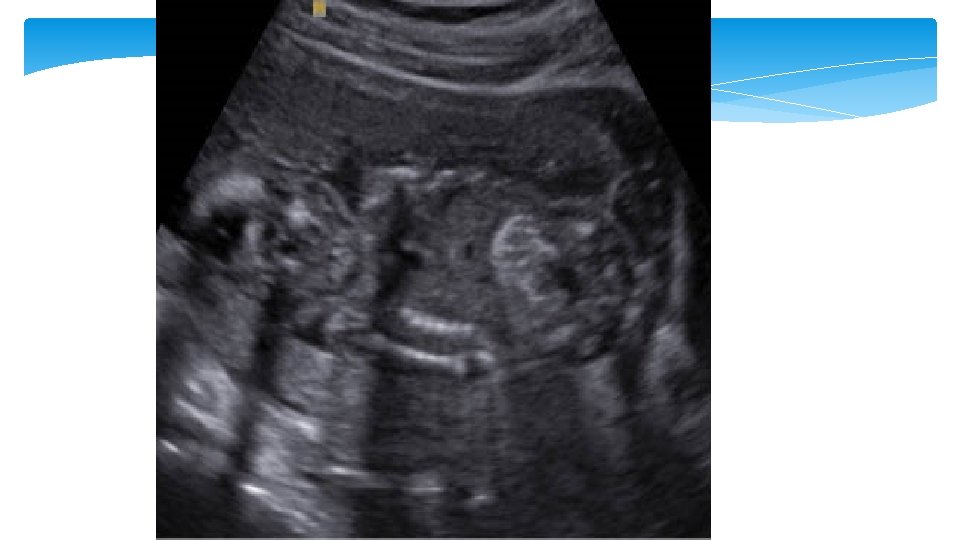

Echogenic bowel The bowel is considered to be echogenic when it is bright compared to the adjacent bone. A echogenic bowel is reported to be present in 0. 2– 1. 4% of 2 nd trimester USs and be diffuse or focal. When present it can be associated with aneuploidy (trisomy 21), congenital infection (CMV, toxoplasmosis, parvovirus), cystic fibrosis, intra amniotic bleeding, IUGR

Soft marker Second trimester: echogenic bowel Second trimester: thickened nuchal fold Second trimester: mild ventriculomegaly Imaging criteria Aneuploidy association Management Fetal small bowel as echogenic as bone • LR 5. 5 to 6. 7 for Down syndrome • Associated with aneuploidy, intraamniotic bleeding, CF, CMV 1. Further counseling 2. Offer CMV, CF, and aneuploidy screening or diagnostic testing ≥ 6 mm from outer edge of the occipital bone to outer skin in the midline • LR 11 to 18. 6 with 40 to 50% sensitivity and >99% specificity for Down syndrome • Most powerful secondtrimester marker 1. Detailed anatomic survey 2. Further detailed genetic counseling and aneuploidy screening or diagnostic testing • Associated with aneuploidy • LR 25 for Down syndrome 1. Genetic counseling 2. Second-trimester detailed anatomic ultrasound evaluation 3. Consider diagnostic testing for aneuploidy and CMV 4. Repeat ultrasound in third trimester Lateral ventricular atrial measurement between 10 to 15 mm